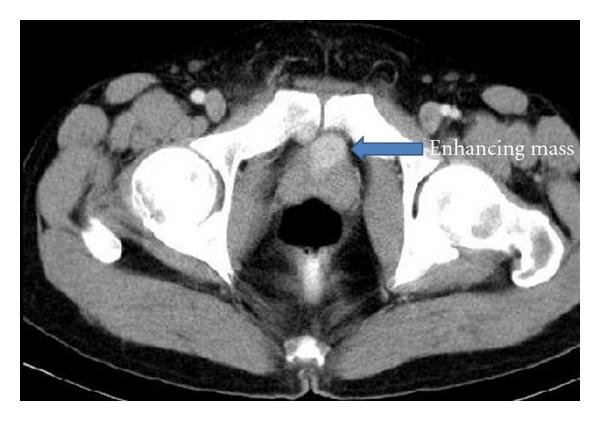

A 39-year-old male presented with recurrent attacks of gross painless haematuria for 5 months. The patient has a history of partial cystectomy for paraganglioma 10 years prior to the presentation. The pathological report stated that the surgical margin was negative. The urine catecholamine level postresection was normal. He was followed for one year postoperatively with cystoscopic examination without any sign of recurrence. The patient does not have similar history in the family. Regarding his second presentation, the patient had no attacks of headache, sweating, palpitation, anxiety, or postmicturition syncope. His blood pressure was within normal range. Urine analysis revealed red blood cells in large quantity. Plasma metanephrines and urine vanillylmandelic acid (VMA) levels were within normal limits. Abdominal CT scan showed a 32cm oval-shaped homogenous anterior bladder wall mass. The mass showed intense uniform enhancement with contrast study. There was no associated lymphadenopathy or invasion to the surrounding pelvic structures (Figure 1).